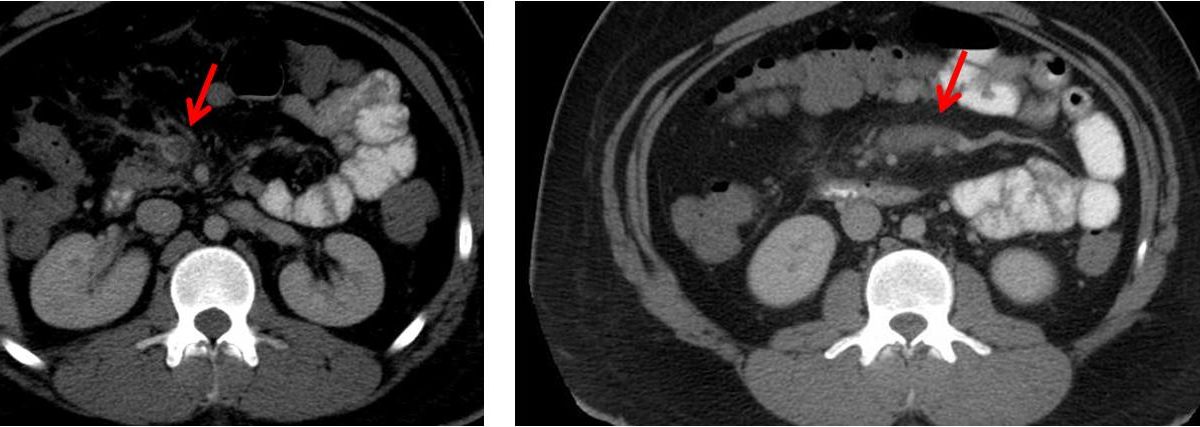

There are no formal guidelines for the treatment of mesenteric venous thrombosis. Therefore mesenteric venous thrombosis should be suspected when patients with previous thrombotic episodes or coagulopathy present with acute abdominal symptoms. A CT scan of the abdomen showed superior mesenteric vein thrombosis arrow. Mesenteric vein thrombosis almost always involves the distal small intestine superior mesenteric venous drainage and rarely involves the colon inferior mesenteric venous drainage. Both entities diagnostic and treatment guidelines share disparities and similarities that may. Clinically separate from portal venous thrombosis due to a higher proportion of associated thrombophilic disorders and intestinal infarction SMV thrombosis warrants a distinct approach to management.

Acute mesenteric ischemia AMI may be defined as a sudden interruption of the blood supply to a segment of the small intestine leading to ischemia cellular damage intestinal necrosis and eventually patient death if untreated AMI may be non-occlusive NOMI or occlusive with the primary etiology further defined as mesenteric arterial embolism 50. A CT scan of the abdomen with coronal view showed superior mesenteric vein thrombosis arrow. Acute mesenteric ischemia AMI may be defined as a sudden interruption of the blood supply to a segment of the small intestine leading to ischemia cellular damage intestinal necrosis and eventually patient death if untreated AMI may be non-occlusive NOMI or occlusive with the primary etiology further defined as mesenteric arterial embolism 50. A CT scan of the abdomen showed superior mesenteric vein thrombosis arrow. 10 Further recurrent bleeding was.

Mesenteric venous thrombosis MVT is a disorder in which a local blood coagulation impairs the venous return of the bowel. A CT scan of the abdomen with coronal view showed superior mesenteric vein thrombosis arrow. If the patient is clinically unstable immediate abdominal exploration. The anatomic site of involvement in acute mesenteric venous thrombosis is most often ileum 64 to 83 percent or jejunum 50 to 81 percent followed by colon 14 percent and duodenum 4. Mesenteric vein thrombosis almost always involves the distal small intestine superior mesenteric venous drainage and rarely involves the colon inferior mesenteric venous drainage.

1 2 Extension to mesenteric venous arches causes intestinal infarction with a reported mortality of up to 50. Mesenteric venous thrombosis MVT is a disorder in which a local blood coagulation impairs the venous return of the bowel. The superior mesenteric vein is enlarged as a result of the thrombosis curved arrow and has a sharply defined wall with a rim of increased density. Clinically separate from portal venous thrombosis due to a higher proportion of associated thrombophilic disorders and intestinal infarction SMV thrombosis warrants a distinct approach to management. A CT scan of the abdomen showed superior mesenteric vein thrombosis arrow.

The superior mesenteric vein is enlarged as a result of the thrombosis curved arrow and has a sharply defined wall with a rim of increased density. This condition can lead to venous engorgement and mesenteric ischemia and. Mesenteric venous thrombosis MVT is a disorder in which a local blood coagulation impairs the venous return of the bowel. In addition to accepted risk factors of hypercoagulability and local-abdominal processes increased intra-abdominal pressure intraoperative manipulation or extrinsic anatomical compression might also contribute to venous compromise. Venous complications usually manifest as thrombosis of the superior mesenteric or portal vein.